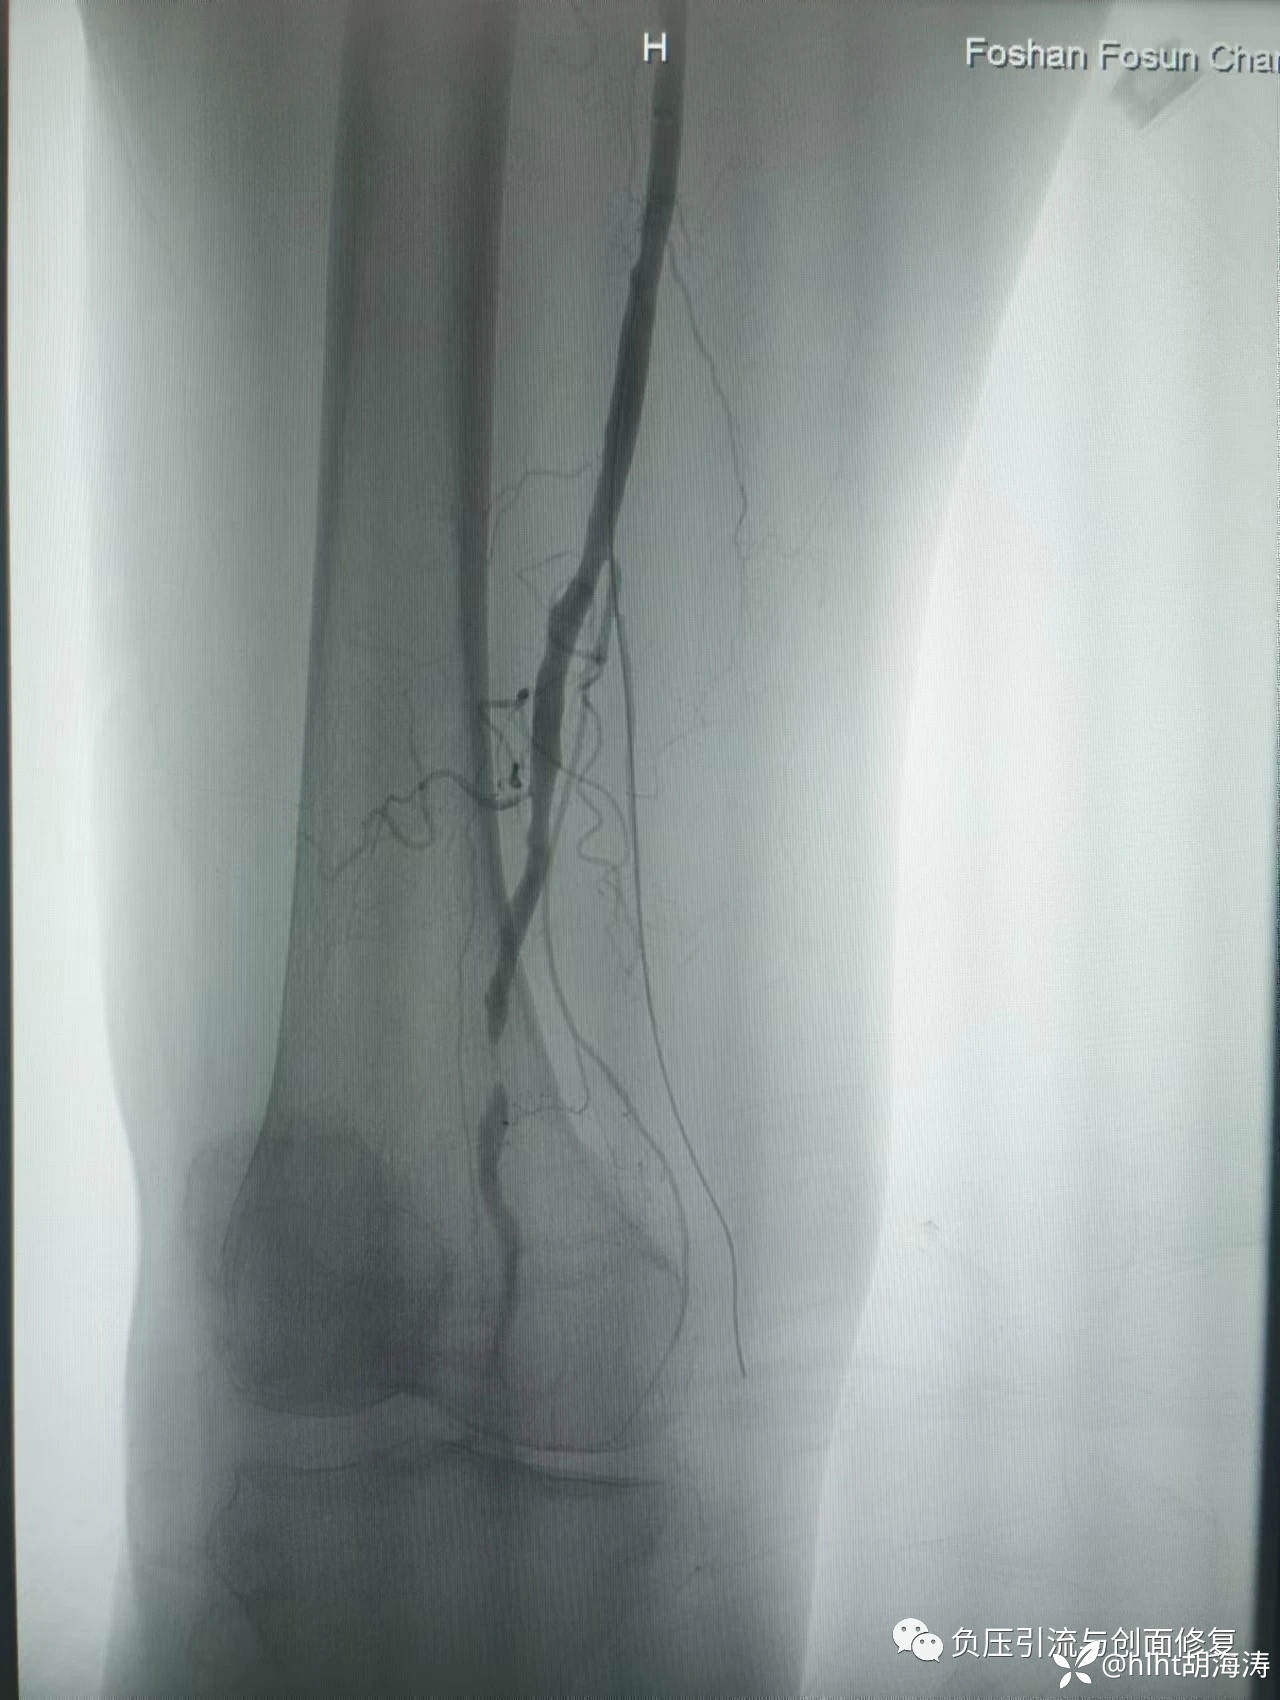

造影:发现股动脉远端重度狭窄,腓动脉和胫后动脉完全闭塞,胫前动脉轻中度狭窄部分重度狭窄;

患者运气也很好:导丝顺利经过各闭塞和狭窄部位,到达足背动脉;

球囊扩张从2mm开始,胫前动脉到4mm,股动脉远端到6mm,再次造影,血流通畅,没有夹层,就没放支架,单纯球囊扩张,手术时间90分钟;

术后右足暖和,疼痛明显减轻,患者当晚睡了一个好觉;